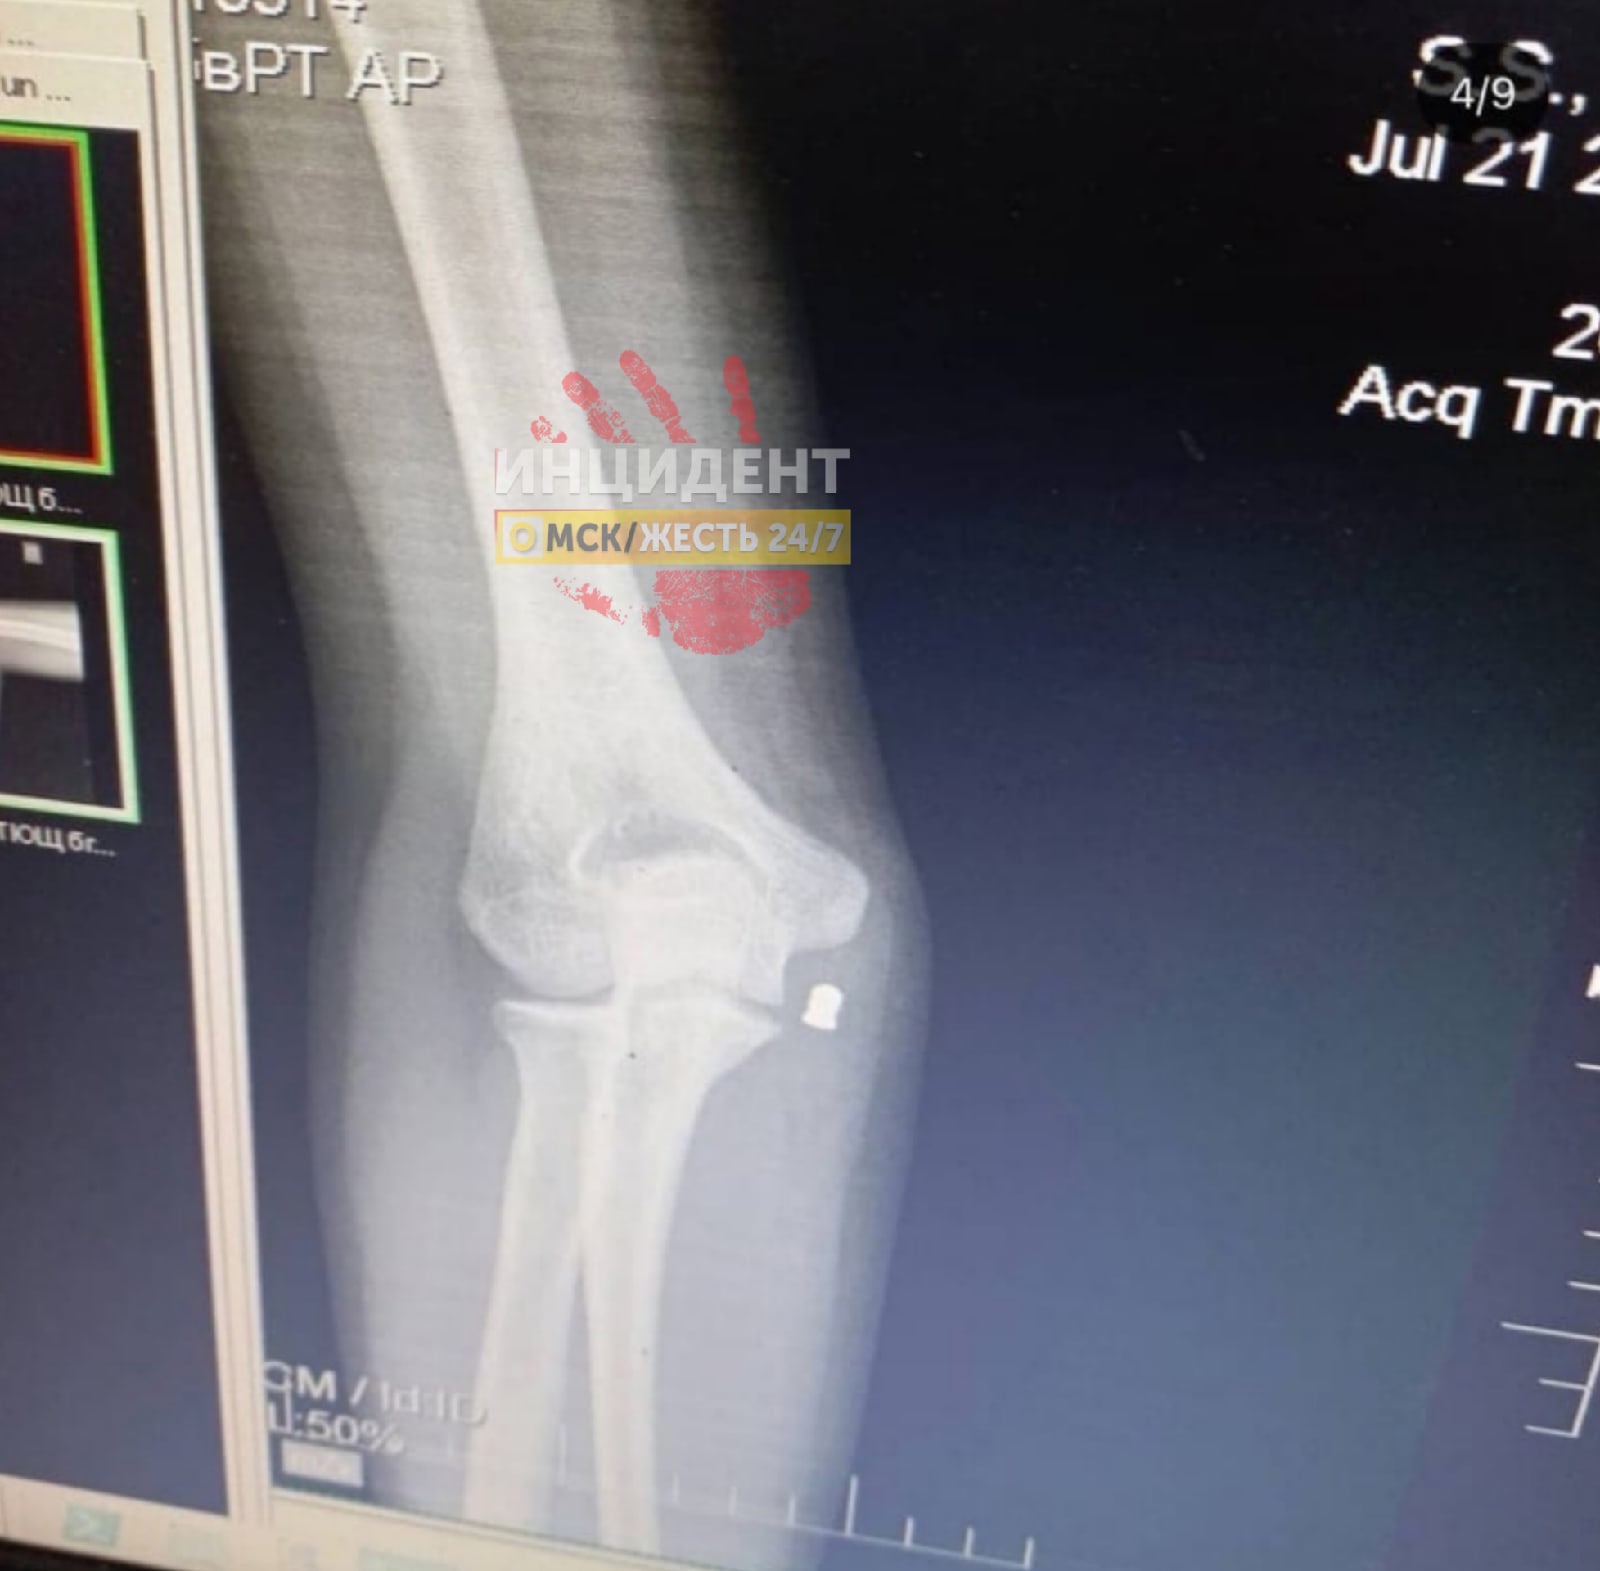

«Какой-то человек начал стрелять по 3 девочкам: одной 12 лет, другим по 15. Полицейские сказали, что пули были сплавлены самостоятельно, - сообщил «Инцидент Омск». - Пули, кстати, остались в руках, поэтому этой ночью им их доставали под общим наркозом. На первом фото видно, как пуля зашла и осталась под кожей».

В то же время новостной ресурс Mash сообщает, что девочек было действительно трое и гуляли они по виадуку на улице Демьяна Бедного. Во время прогулки девушки фотографировались и позировали друг другу. Злоумышленник, вероятно, в это время за ними наблюдал. В какой-то момент самая младшая из подруг решила показать остальным удачный кадр в телефоне, и ощутила выстрел. «Пуля попала в запястье и осталась в руке. Сначала подростки подумали, что взорвался аккумулятор, но раздался второй выстрел — вторую девочку ранило в локоть. В больнице обеим наложили швы, операция у младшей была сложнее — пуля оказалась рядом с веной», - сообщает источник.